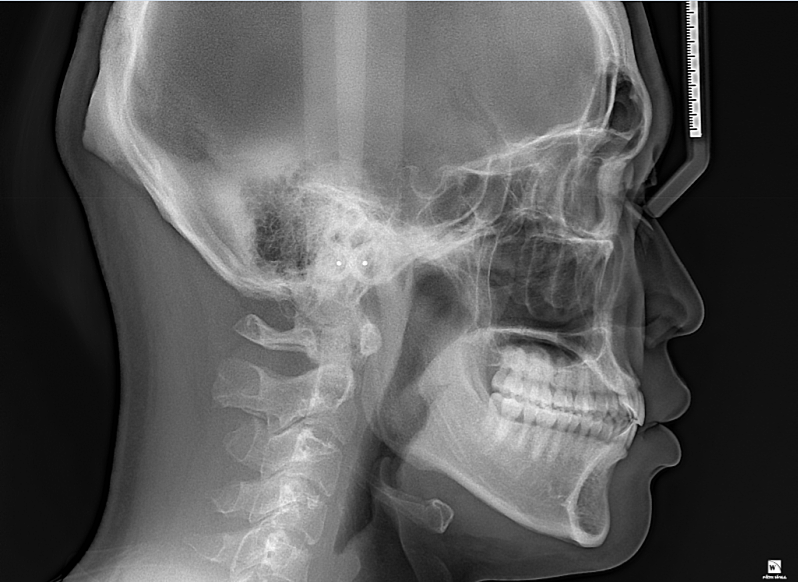

턱이 나오거나 돌출된건가요??

1.제 턱이 정상사람 보다 앞으로 나오거나 돌출된 건가요???

2.이런 얼굴은 발치교정하면 얼굴이 길어보일 수 있나요????

• 1번 째 사진

1. 말씀하신 것은 연조직까지 같이 평가해야 합니다. 골격상에는 앞으로 튀어나왔다고 하더라도 연조직에서 그렇게 보이지 않을 수 있습니다. 또한 계측된 값들이 필요하며 교정치과 방문 후 수치를 알아보시길 바랍니다.

2. 발치 교정을 통해 얼굴이 길어질지는 안모에 대한 자료도 필요합니다.

사진상으로는 아래턱이 크게 문제가 있어 보이진 않습니다. 궁금하시다면 교정진단을 통해서 정상범위에서 얼마만큼 차이가 있는지 확인할수 있습니다.